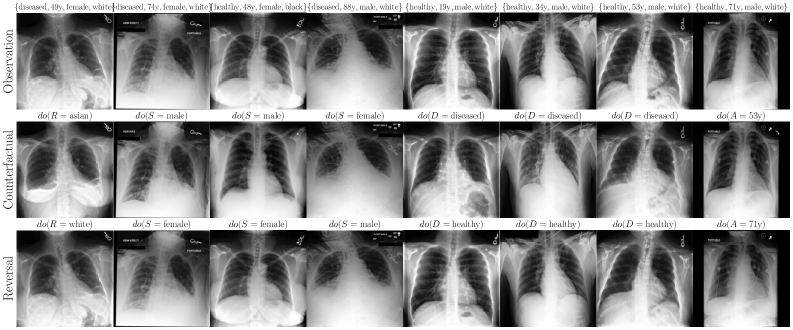

6.2 Case Study: Chest X-ray Imaging Counterfactuals

To extend our study to high-dimensional settings, we conduct experiments on MIMIC-CXR (Johnson et al., 2019), a widely used dataset for counterfactual inference. Our assumed causal graph follows the baselines (Ribeiro et al., 2023; Xia et al., 2024), and includes Sex (), Race (), Age () and Disease () variables, where , and cause the X-ray image . To parameterise our flow models, we use a streamlined version of Dhariwal and Nichol (2021)’s UNet architecture (see Appendix F for details). Table 2 and Figure 4 report our main results. We observe substantial improvements over baselines (Ribeiro et al., 2023; Xia et al., 2024) using our flows, across all three counterfactual soundness axioms, and without requiring any costly counterfactual fine-tuning or classifier(-free) guidance. That said, this alone does not imply causal validity. In Appendix F, we report additional comparisons and ablations. We observe performance trade-offs: for instance, OT-Flow (which assumes Markovianity) outperforms on race interventions but underperforms Flow on disease interventions, suggesting non-Markovian interaction effects or a subpar OT approximation. Notably, our Markovian OT coupling substantially improves over the Naive OT flow baseline.